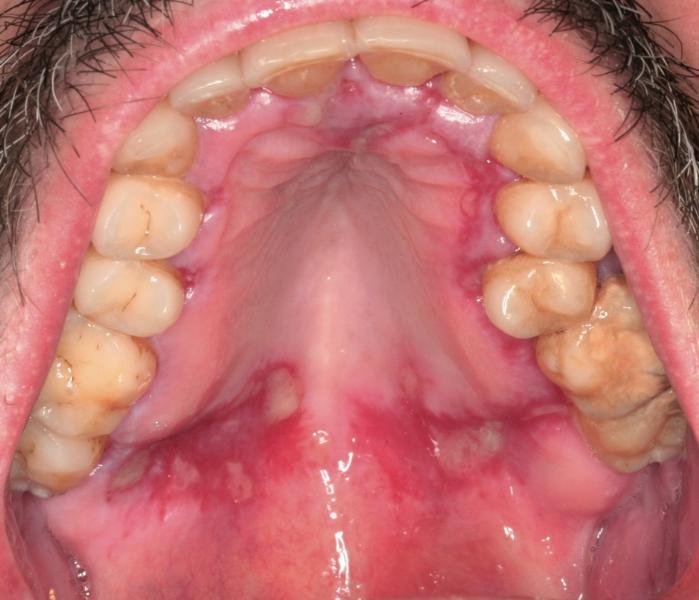

CASO CLÍNICO LXII

Fibromatosis gingival, (fibromatosis del paladar)